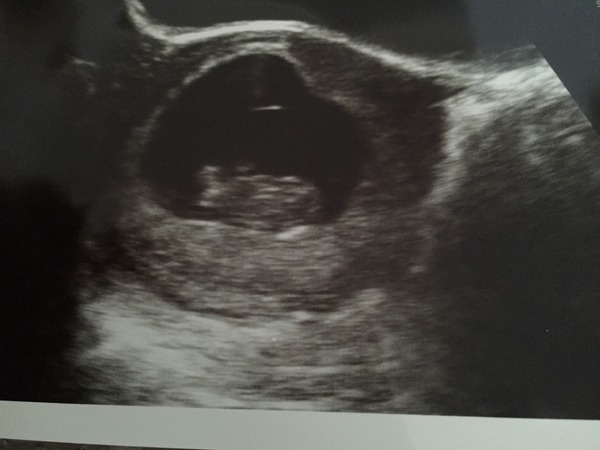

Just to update you all, I've had my scan and everything seems fine. Couldn't get a clear picture but we could see the heart beating and snowflake was moving around. Baby is also measuring correct EDD 30/5/16 It's such a huge relief, I'm now going to enjoy my symptom free pregnancy while it lasts.